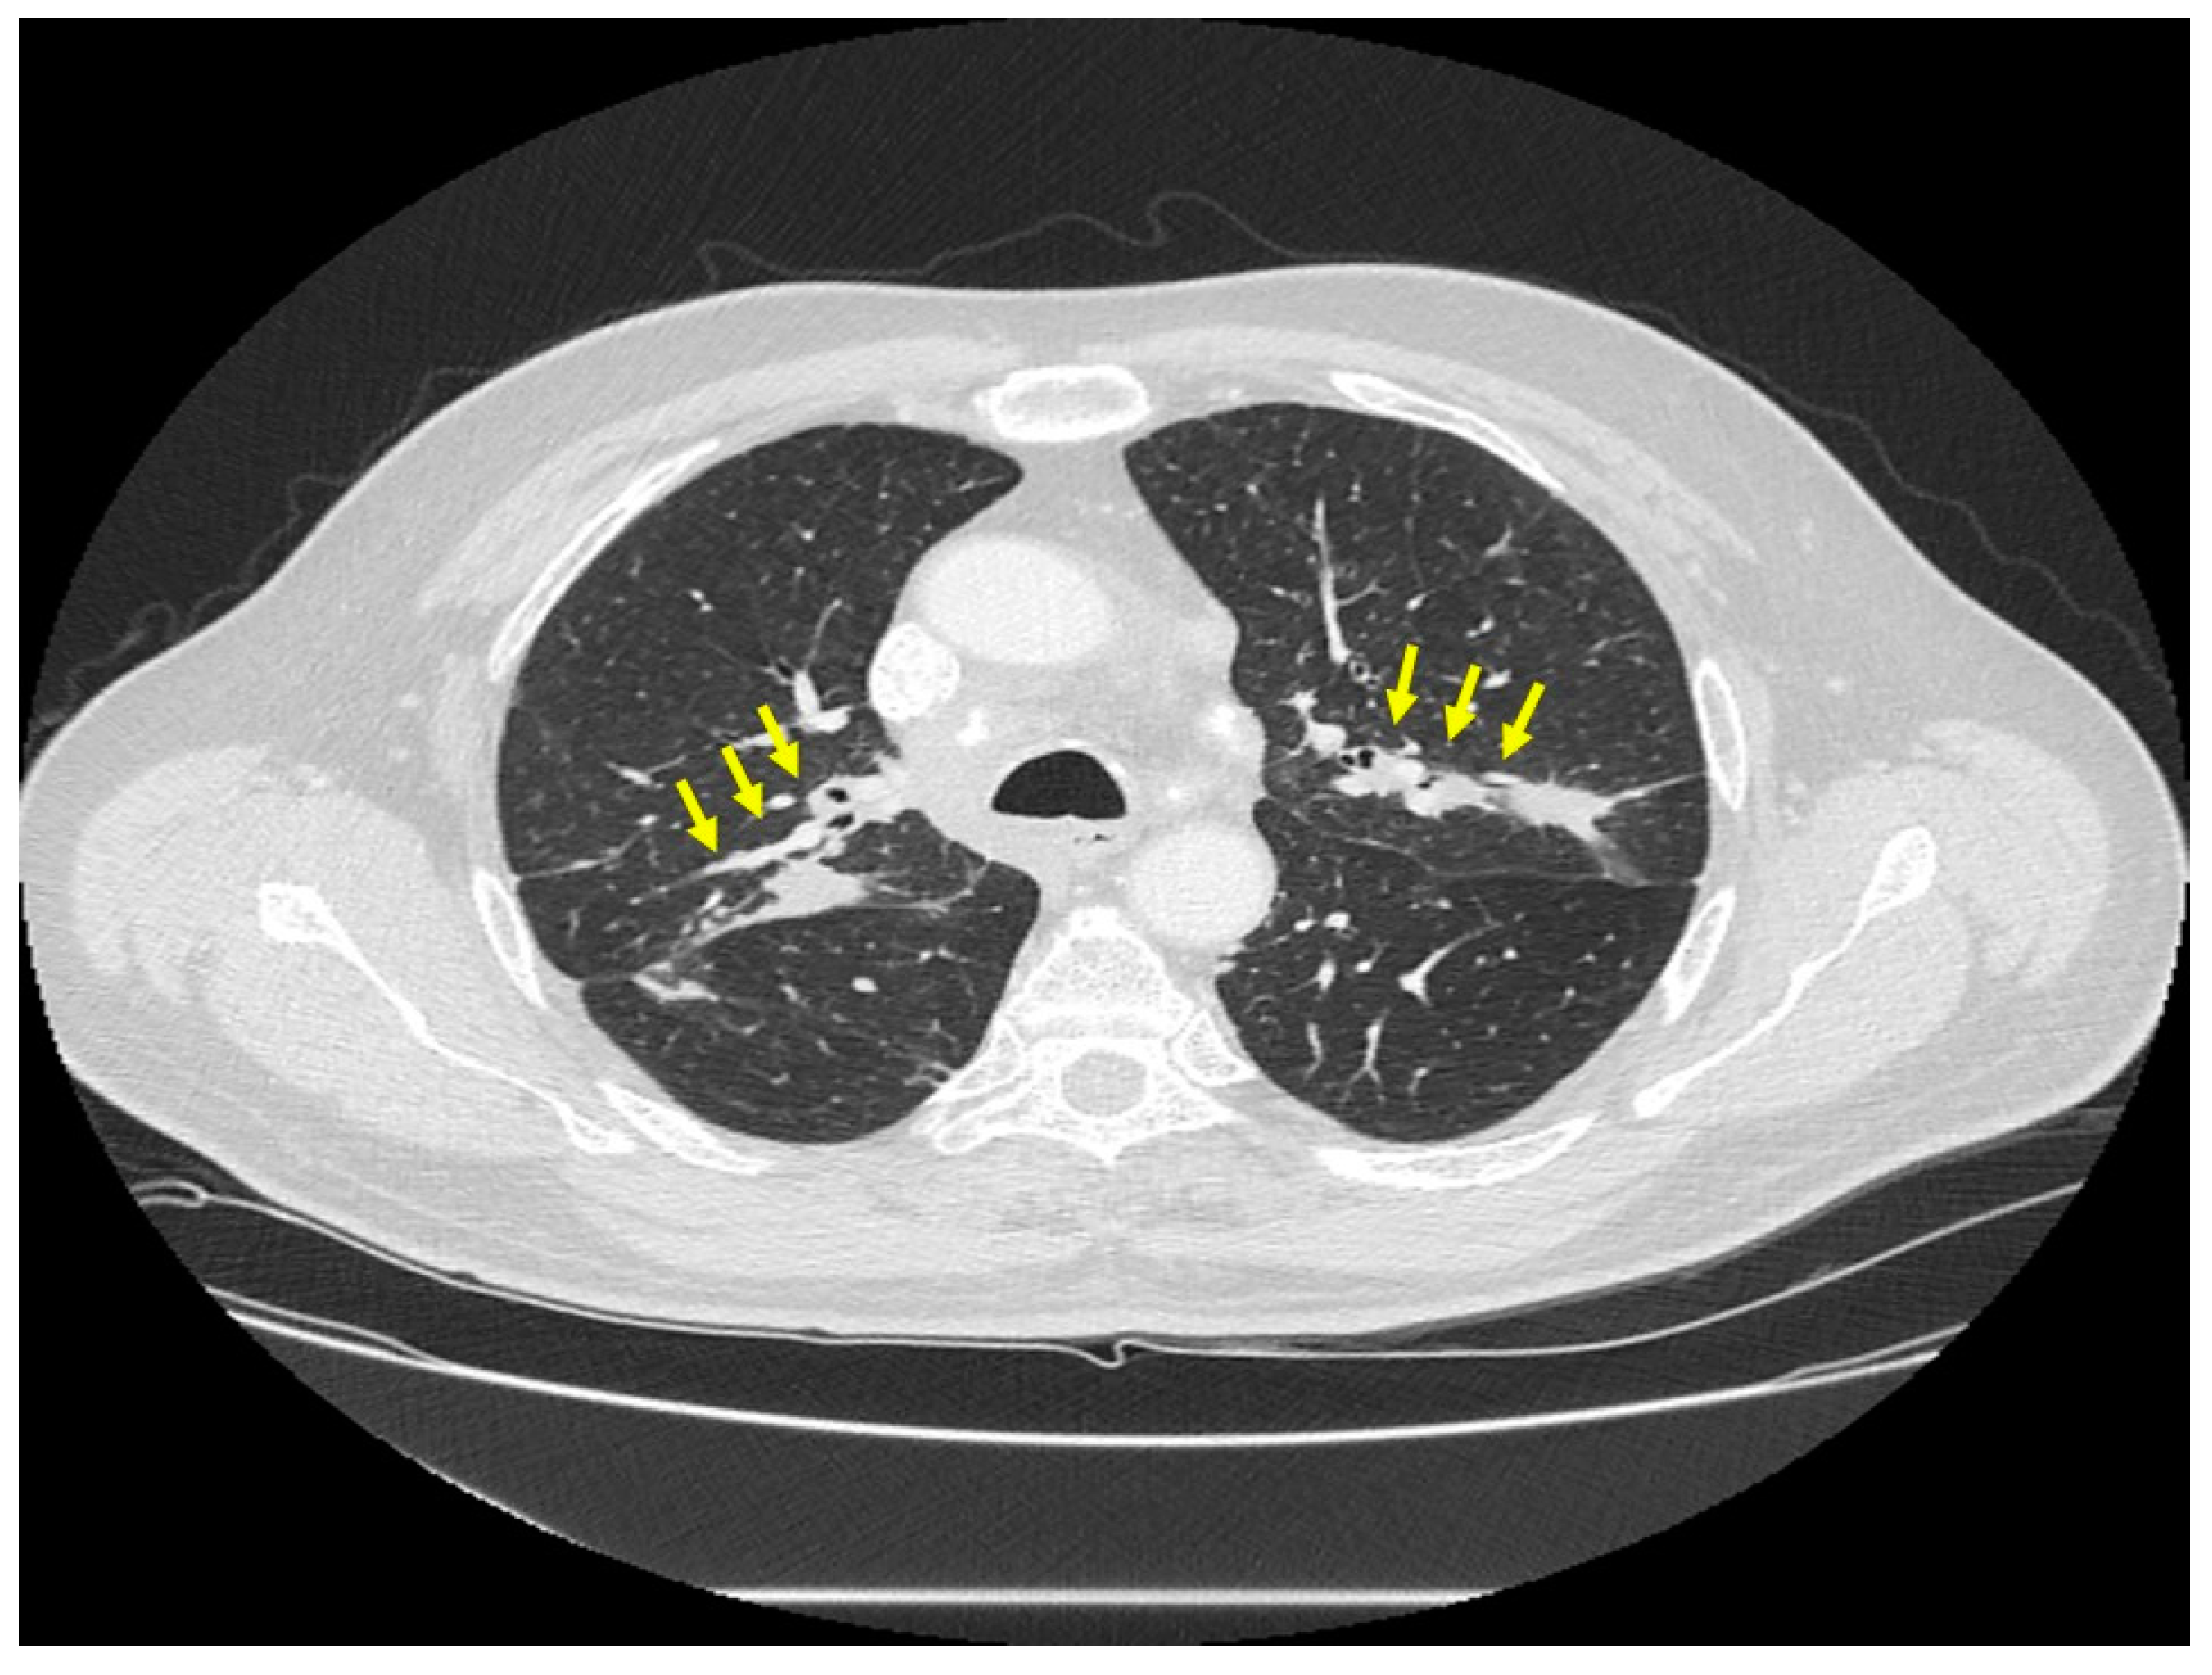

Figure 2.

Chest CT scan image of a patient with pulmonary sarcoidosis, demonstrating lung opacities from granulomatous inflammation around airways (arrows).